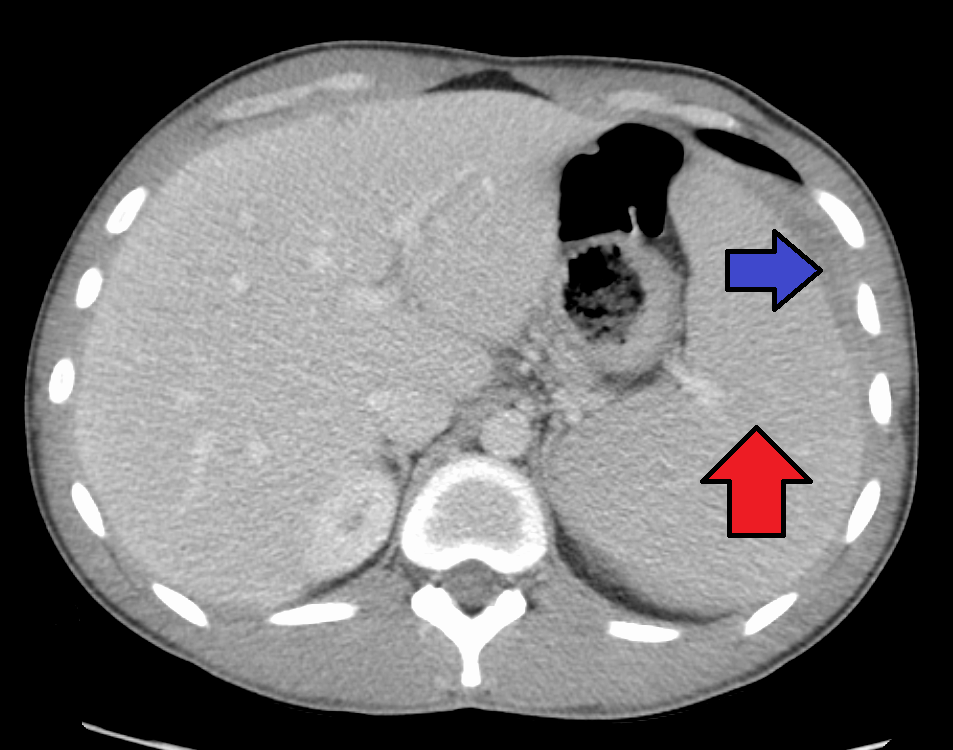

대부분의 감염성 단핵구증은 자연적으로 회복되지만, 드물게 합병증이 나타날 수 있다. 비장 파열, 용혈성 빈혈, 수막염, 뇌염, 횡단척수염, 길랭-바레 증후군 등이 발생할 수 있다.[26][63][64][43][65]비장 비대는 발병 2~3주차에 흔하게 나타나지만, 신체 검사로는 뚜렷하게 나타나지 않을 수 있다. 드물게 비장 파열이 발생할 수 있다.[26] 또한 약간의 간 비대증이 나타날 수 있으며,[23] 황달은 간혹 발생한다.[30][27]

비장 비대와 경부, 겨드랑이, 서혜 림프절의 림프절 종창은 감염성 단핵구증 진단을 의심하는 데 가장 유용하다. 반면에 경부 림프절 종창이 없고 피로가 나타나지 않는다면 감염성 단핵구증이 아니라고 생각할 수 있다. 비장 비대를 감지하는 신체 검사의 무감도는 감염성 단핵구증에 대한 증거로 사용해서는 안 된다는 것을 의미한다.[23] 신체 검사에서 구개의 점상 출혈이 나타날 수도 있다.[23]4. 2. 혈액 검사

비장 파열의 위험을 줄이기 위해 전문가들은 질병 발병 후 최소 3~4주 동안 또는 치료 의사가 결정한 비장 비대 소실 시점까지 접촉 스포츠 및 기타 격렬한 신체 활동, 특히 복부 압력 증가 또는 발살바 수기 (예: 조정 또는 역도)를 피하도록 권고한다.[23][52] 간비종이 심한 경우에는 복부에 충격을 받아 비장 파열이 일어난 사례도 있으므로 안정이 필요하다. 소아 등, 인두통이나 전신 권태감으로 인해 경구 섭취가 불량해진 경우에는 입원하여 수액을 투여할 필요가 있다.